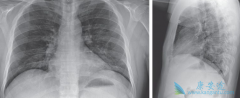

近日,美国首例新型冠状病毒(COVID-19)患者在服用抗病毒药瑞德西韦 ( Remdesivir )后症状得到了显著改善的消息受到了人们的广泛关注。瑞德西韦由美国吉利德公司开发,起初的研发目的是用于防治埃博拉病毒感染,而目前被证明对于新冠病毒有立竿见影的疗 ...

到目前,感染 新冠肺炎病毒 (HCoV)后还没有有效的抗病毒治疗药物,在重症病例中对肺和其他器官功能支持仍为主要治疗手段。糖皮质激素的使用仍然是一个有争议的话题,一般认为糖皮质激素并不能改善预后,可能会导致病毒清除延迟。 体外研究显示干扰 ...